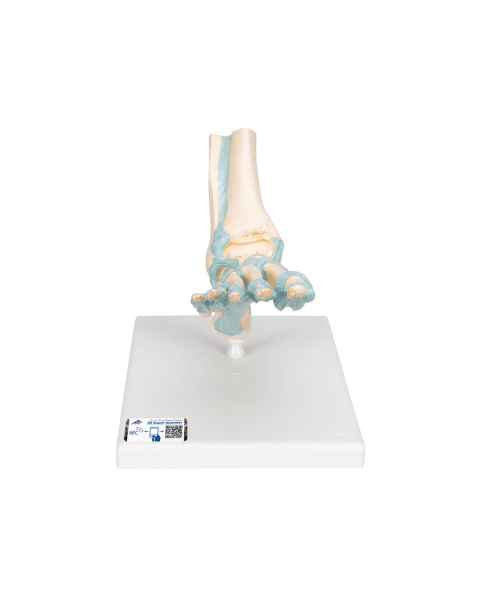

Extremity Models

While the majority of vital human organs are located inside of the head and torso, human appendages are just as important in terms of day-to-day functionality. In order to depict the parts and workings of these limbs, doctors and teachers rely upon extremity anatomical models.

With the assistance of extremity anatomy models, patients and students have a tangible tool to better understand their appendages, as well as potential injuries that are afflicting them or require treatment. Our extensive selection of extremity models includes arm anatomical models, foot models, hand anatomy models, and leg models.